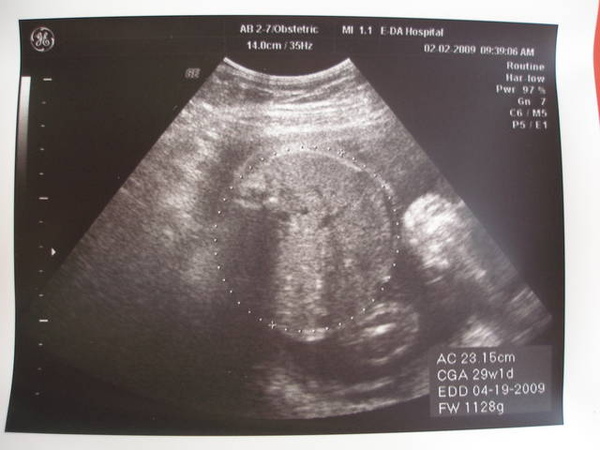

因為寶寶現在比較大隻了,只能量頭圍&肚圍來得知他的體重

這次量的是頭頭

目前是26W的我,但體重已經是29W的重量,柚子已經有1128G

原本的預產期是5月6日,現在足足早了半個月耶